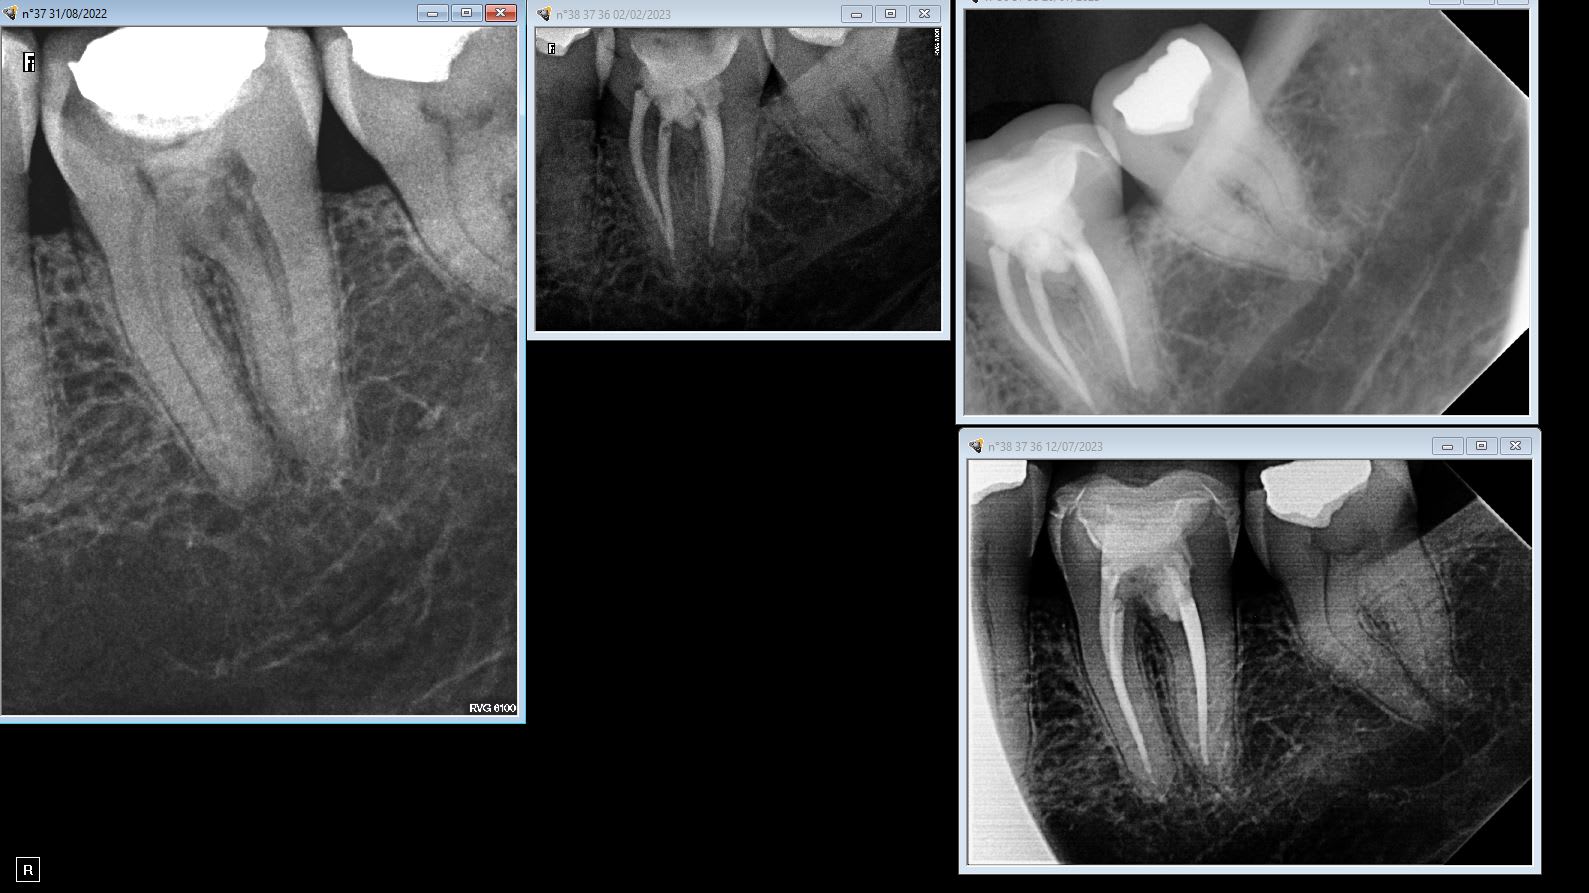

Tu as une radio de ce qu’il t’a fait ? 2h30 c’est vraiment beaucoup !

Il a levé un lambeau en plus pour combler la lésion au MTA.